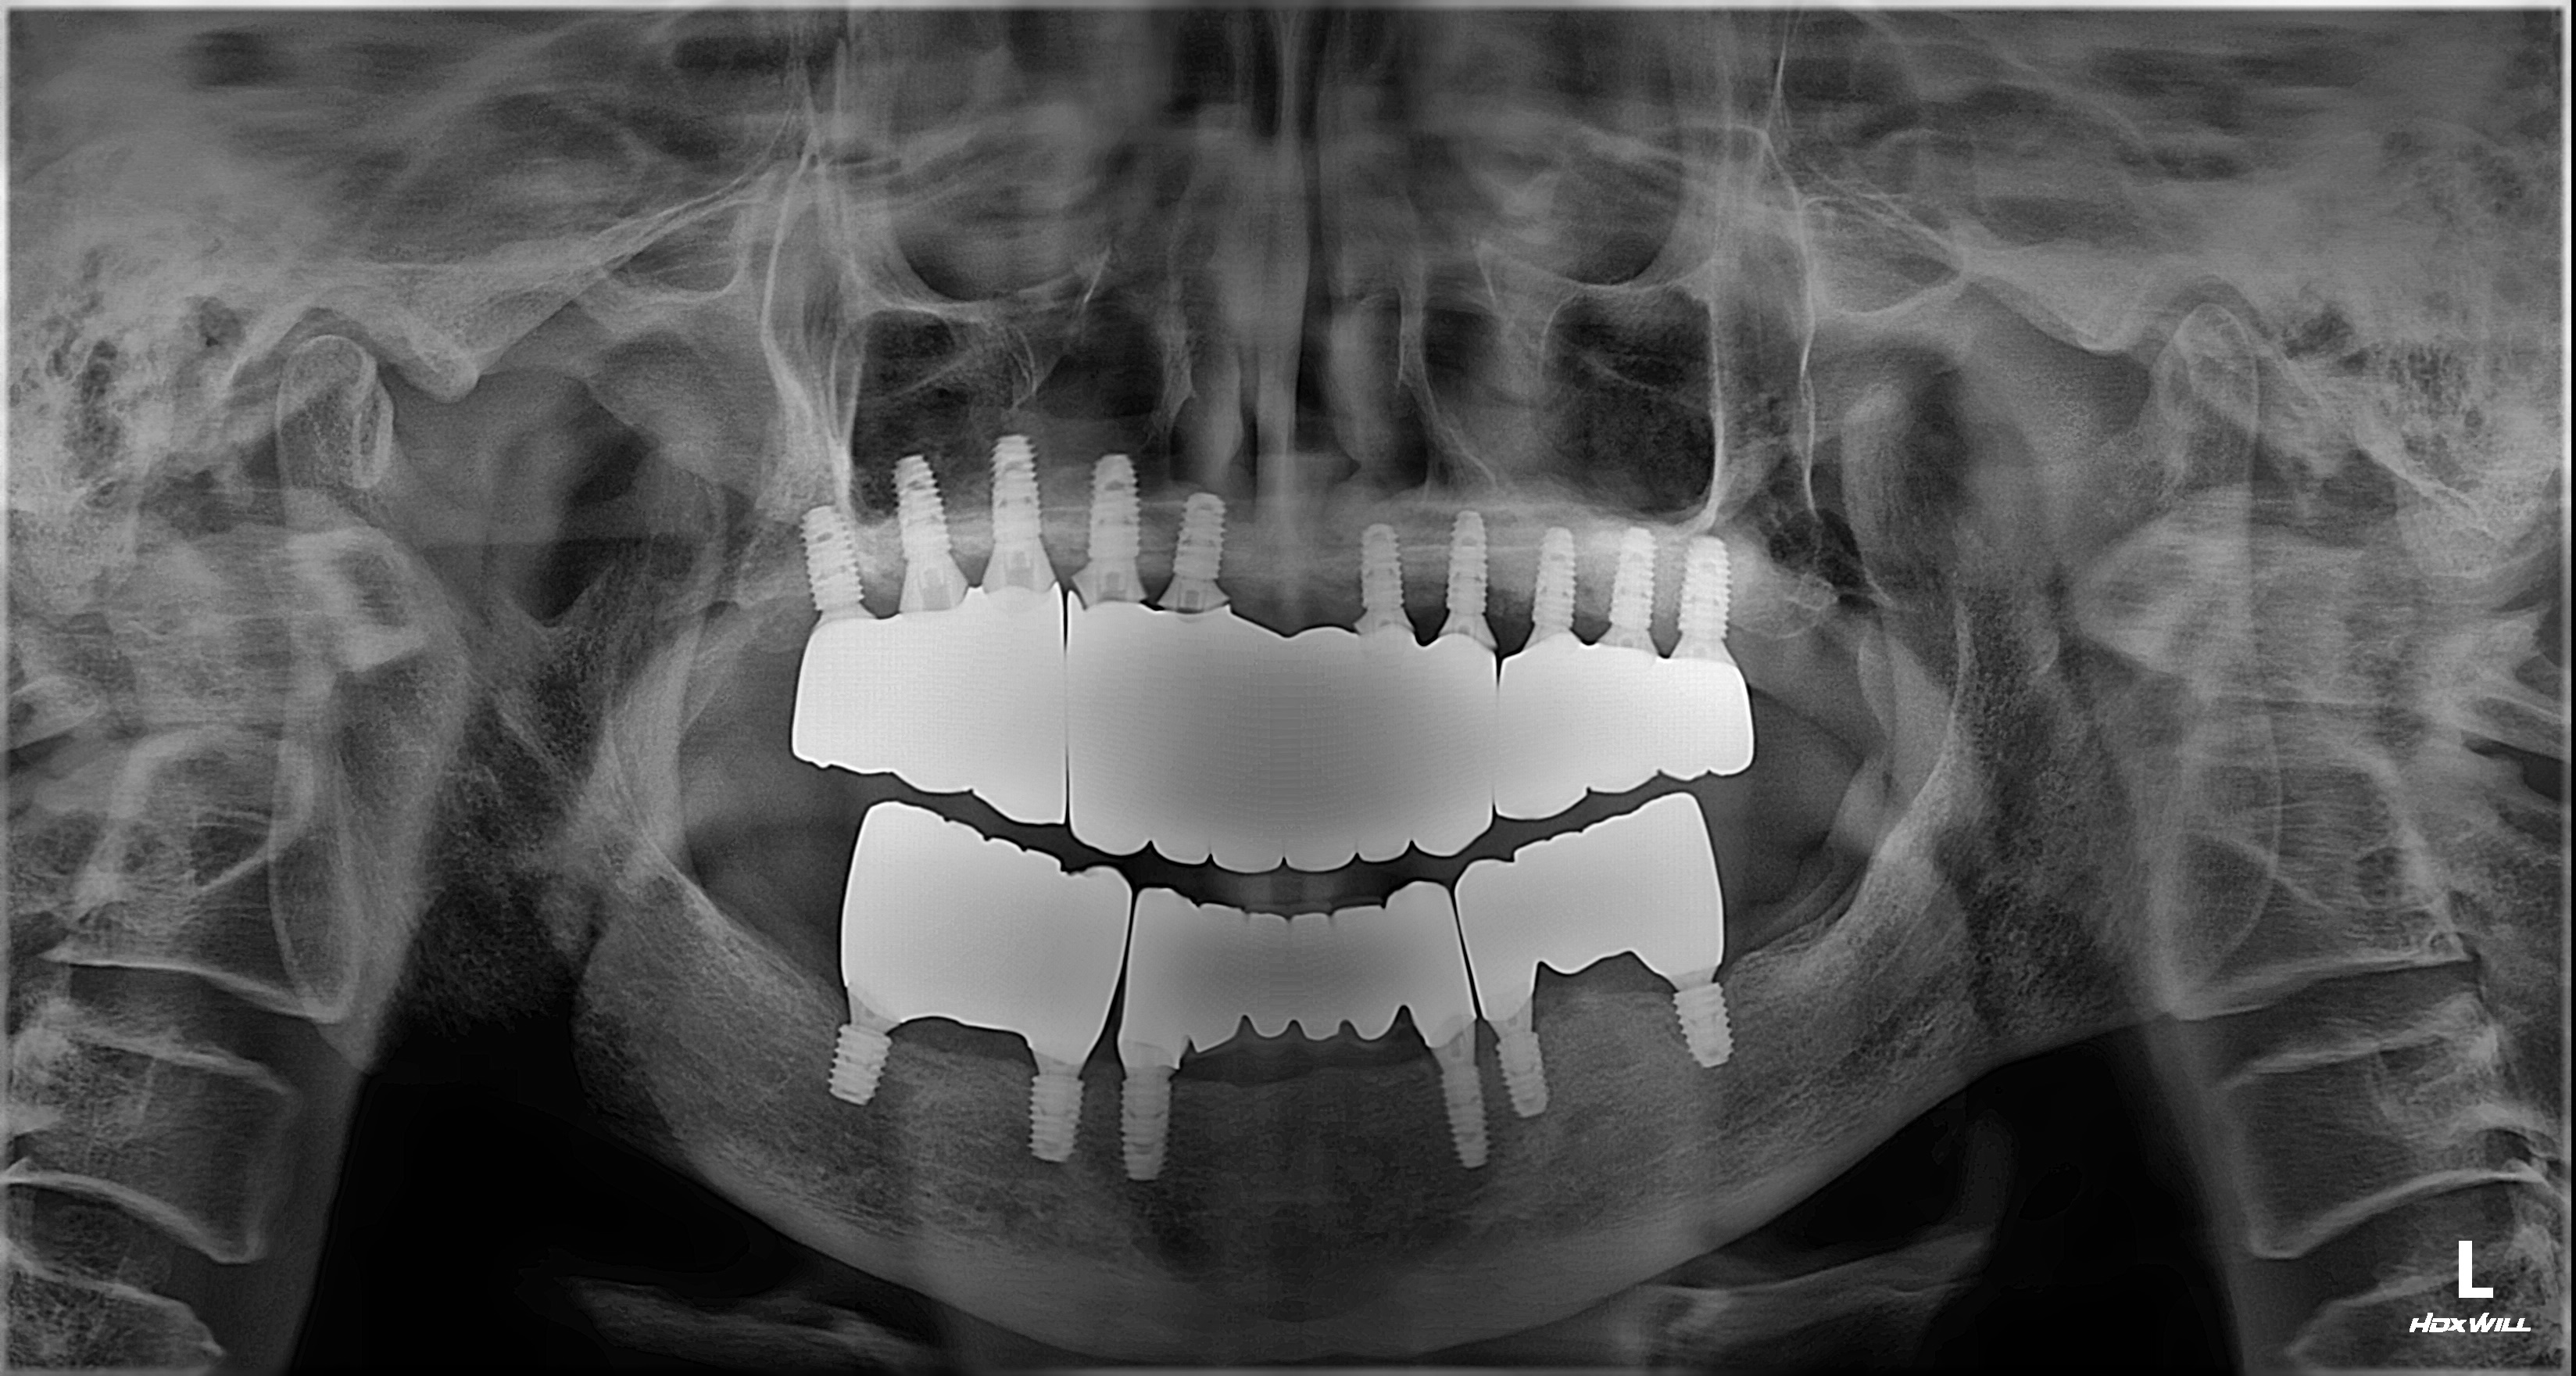

비강거상과 상악동거상을 동반한 전체임플란트 치료 증례 2026-02-20 hit.70 |

촬영일시: 2024.05.03

[ 치료기간: 2024년 05월 03일 ~2025년 03월 14일 ] ※ 365서울앞선치과의원의 모든 컬럼은 각 진료과 의료진이 직접 작성합니다. 365서울앞선치과의원 임상 케이스 게시물은 환자분께 의학적으로 정확하고 상세한 정보를 드리기 위해 각 진료과 의료진이 직접 작성하며, 모든 증례 사진은 본원 의료진이 직접 시술한 증례를 촬영한 것으로, 의료법 제23조, 제56조에 의거하며 환자분의 동의를 얻어 포스팅에 사용하였습니다. 또한 해당 케이스는 본 환자분의 치료 결과이며, 환자 상태에 따라 치료의 결과는 달라질 수 있습니다. |